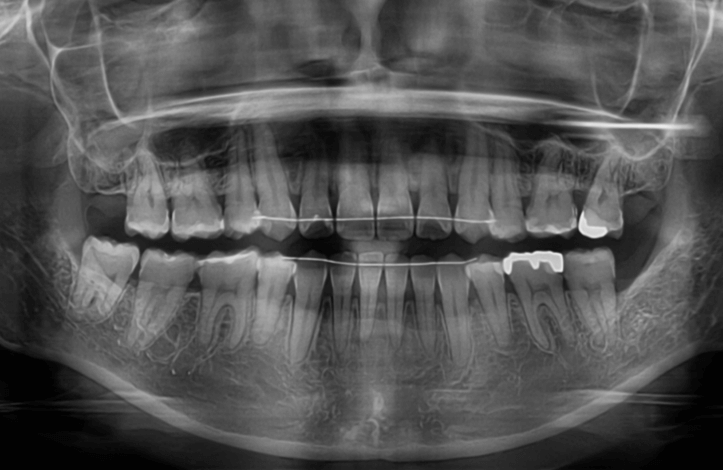

| 年齢・性別 | 15歳の女性 |

|---|---|

| 主訴 | 咬み合わせが逆であること(反対咬合)を気にされて来院された15歳7か月の女性。見た目や機能面の改善を希望されていました。 |

| 治療期間・回数 | 4年4ヶ月・28回 |

| 費用 | 900,000円 |